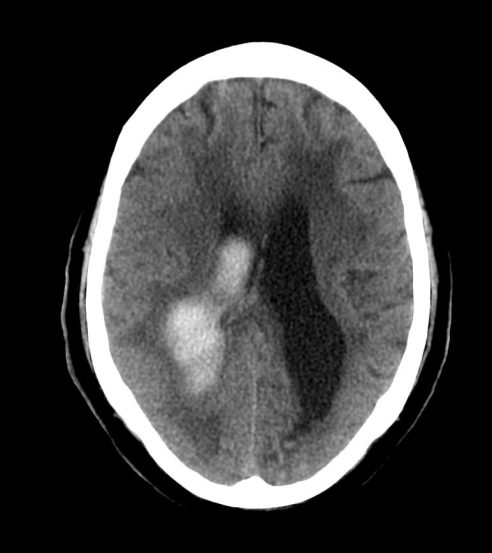

HEMORRAGIAS INTRA AXIALES.

Contusiones.

- Son las lesiones más frecuentes tras un traumatismo, especialmente en personas mayores.

- Son la expresión de laceraciones del parénquima cerebral tras un golpe o contragolpe, dónde suelen ser de mayor tamaño.

- Focos hiperdensos uni o multifocales parcheados y mal definidos. De localización cortical (trauma leve) y/o subcortical (trauma más severo).

- Lóbulo frontal y temporal son localizaciones más frecuentes debido a que el cerebro se desliza sobre la superficie irregular de la fosa craneal anterior y media.

Nota: La contusión y el hematoma constituye el mismo espectro de daños. Las contusiones hemorrágicas se definen como pequeñas hiperdensidades que afecta preferentemente el córtex con o sin edema periférico con relativa normalidad de la sustancia blanca subyacente en el trauma leve. Pueden incrementar en tamaño con el tiempo, lo que se conoce como progresión hemorrágica.